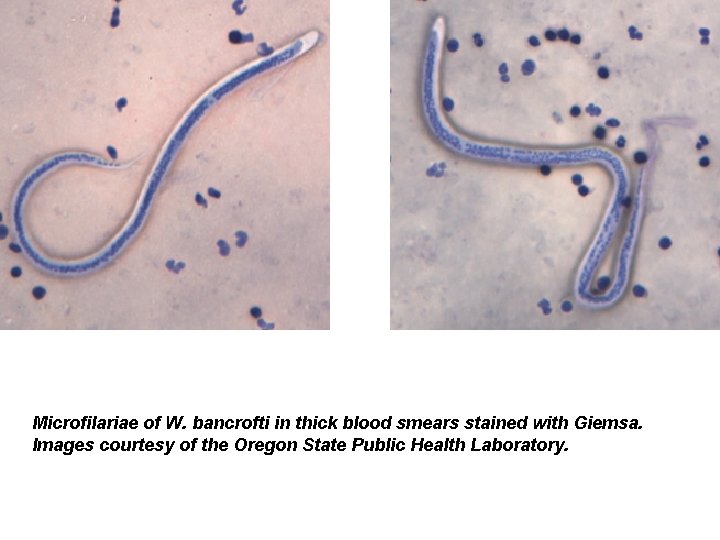

Microfilariae of W. bancrofti in thick blood smears stained with Giemsa. Images courtesy of the Oregon State Public Health Laboratory.